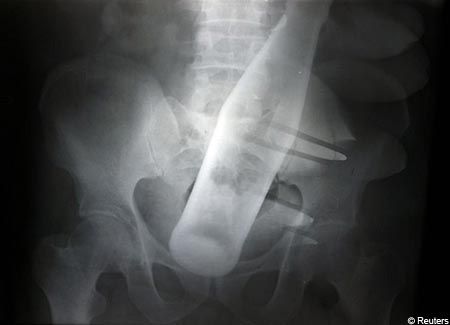

> Nä, var lite långsam, menade flaska i olämplig

> kroppsöppning! Blir det vakum fastnar den, och

> då kan det krävas opreration!